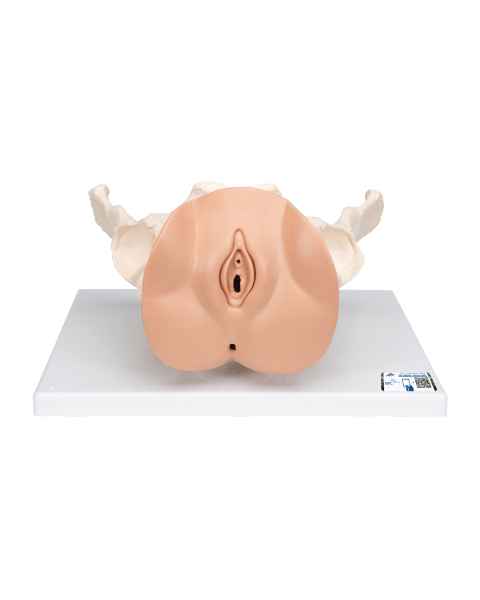

Female anatomical models are an ideal teaching aid to help educate both students and patients. Our extensive selection of female anatomy models includes female pelvic models, pregnancy series models, pelvis skeleton models, delivery/childbirth simulators, clinical breast trainers and self-exam models, uterus/ovary models, and more. Teaching simulators and self-exam models are excellent for educating students and patient education.

For example, the Wearable Breast Self-Exam Model can be easily worn, in order to better train and practice breast self-examination. Our line of prevention and detection models includes the Realistic Left Breast Model, Uterus/Ovary Model with Pathologies, Model of the Female Breast, and the Clinical Breast Trainer. Obstetricians will benefit from owning female anatomy figures of uteri and pelvises with fetuses inside, as well as sets of models that demonstrate the stages of fertilization. Women, particularly first-time mothers, will appreciate having a female education model that clearly illustrates the pregnancy process and what exactly is occurring inside of their body.